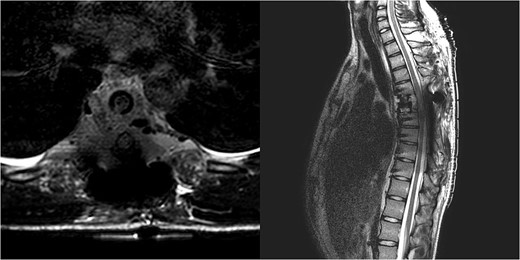

Three and a half years prior to admission to our institution, the patient underwent emergent Th6 vertebroplasty with laminectomy for a radiologically characteristic and histologically confirmed Th6 AVH causing acute thoracic myelopathy with a week-long paresis of the right foot dorsiflexion, performed by another surgeon. A progressive kyphotic deformity of the Th6 vertebrae was observed on radiographic follow-ups, whereby the hypoesthesia on the right anterior thigh persisted (ASIA score D, VAS pain score 7). Follow-up MRI and CT imaging revealed recurrent AVH of the Th6 vertebrae expanding into the spinal canal, leading to newly recognized worsening of myelopathy (Fig. 1). Additionally, a concomitant haemangioma was observed in the right transverse and articular process of Th8 (Fig. 2).

MRI scan of the thoracic spine showing a concomitant haemangioma in the right transverse and articular process of Th8.